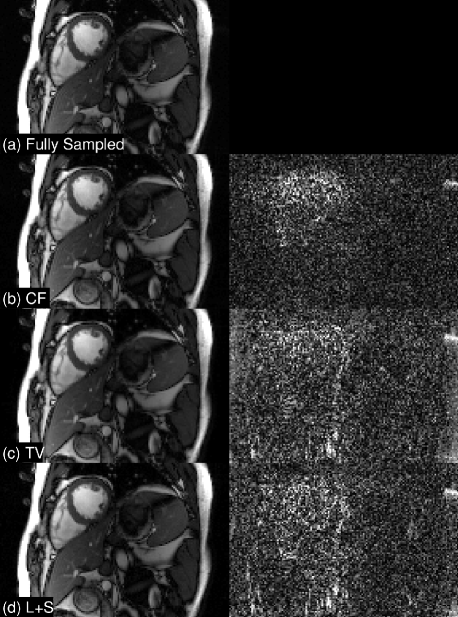

For 2D+t, we retrospectively downsampled three 3T cardiac cine datasets at four different acceleration rates, R and using a variable density sampling pattern [9]. The data were compressed to four virtual coils for faster processing. We fine-tuned parameters for all methods with respect to the first dataset, then applied these parameters to other two datasets. We averaged the reconstruction SNR for the other two different datasets. Quantitative results and representative frames are in Table 2 and Figure 3. We compare to SENSE-based techniques, as SAKE and LORAKS do not provide extension to these cases. The CF is consistently better than L+S [10] and TV [11] by to dB in terms of k-space SNR. With square-root sum of squared coils (SSoS), the margin is even larger.